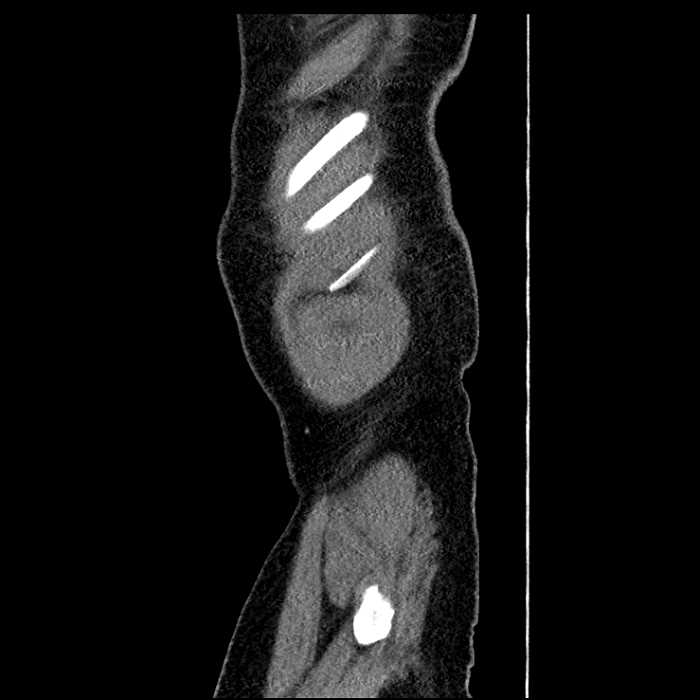

• Mild mural thickening of a segment of the sigmoid colon with adjacent fat stranding and a 1.5 cm fluid and gas collection along the tip of an inflamed diverticulum

• Loss of the normal fat plane between this collection and adjacent loops of small bowel, which demonstrate mural thickening

Acute sigmoid diverticulitis complicated by a small contained perforation and a large abscess in the right hepatic lobe. Additional small subcapsular abscesses along the anterior margin of the left hepatic lobe.

Additionally, loss of the normal fat plane between the peridiverticular collection and adjacent thickened loops of small bowel raises the potential for an enterocolonic fistula.

Hepatic abscess showing the double target sign with low density internally surrounded by a thin inner enhancing rim (red arrow) and ill-defined outer low density rim (yellow arrow). Blue arrow indicates an internal septation. Red arrows: additional smaller subcapsular abscesses. Red arrow: focal contained perforation associated with diverticulitis.